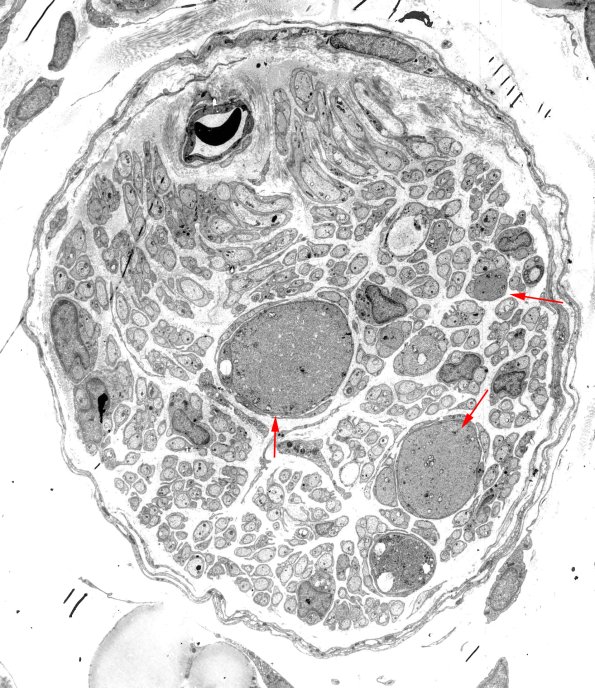

Previously and for many years I worked on an animal model of diabetic autonomic neuropathy in which rats made diabetic with streptozotocin developed an unusual pathology in the sympathetic axons of the ileal mesenteric nerves. I will illustrate this pathology in the next images because it closely resembles the pathology of rare axons encountered in a wide spectrum of human neuropathies.

10A1-5 ---- 10A1,2 A whole mount of the mesenteric nerves of diabetic rats. The entire nerve is ~50 microns in diameter. (electron micrographs)